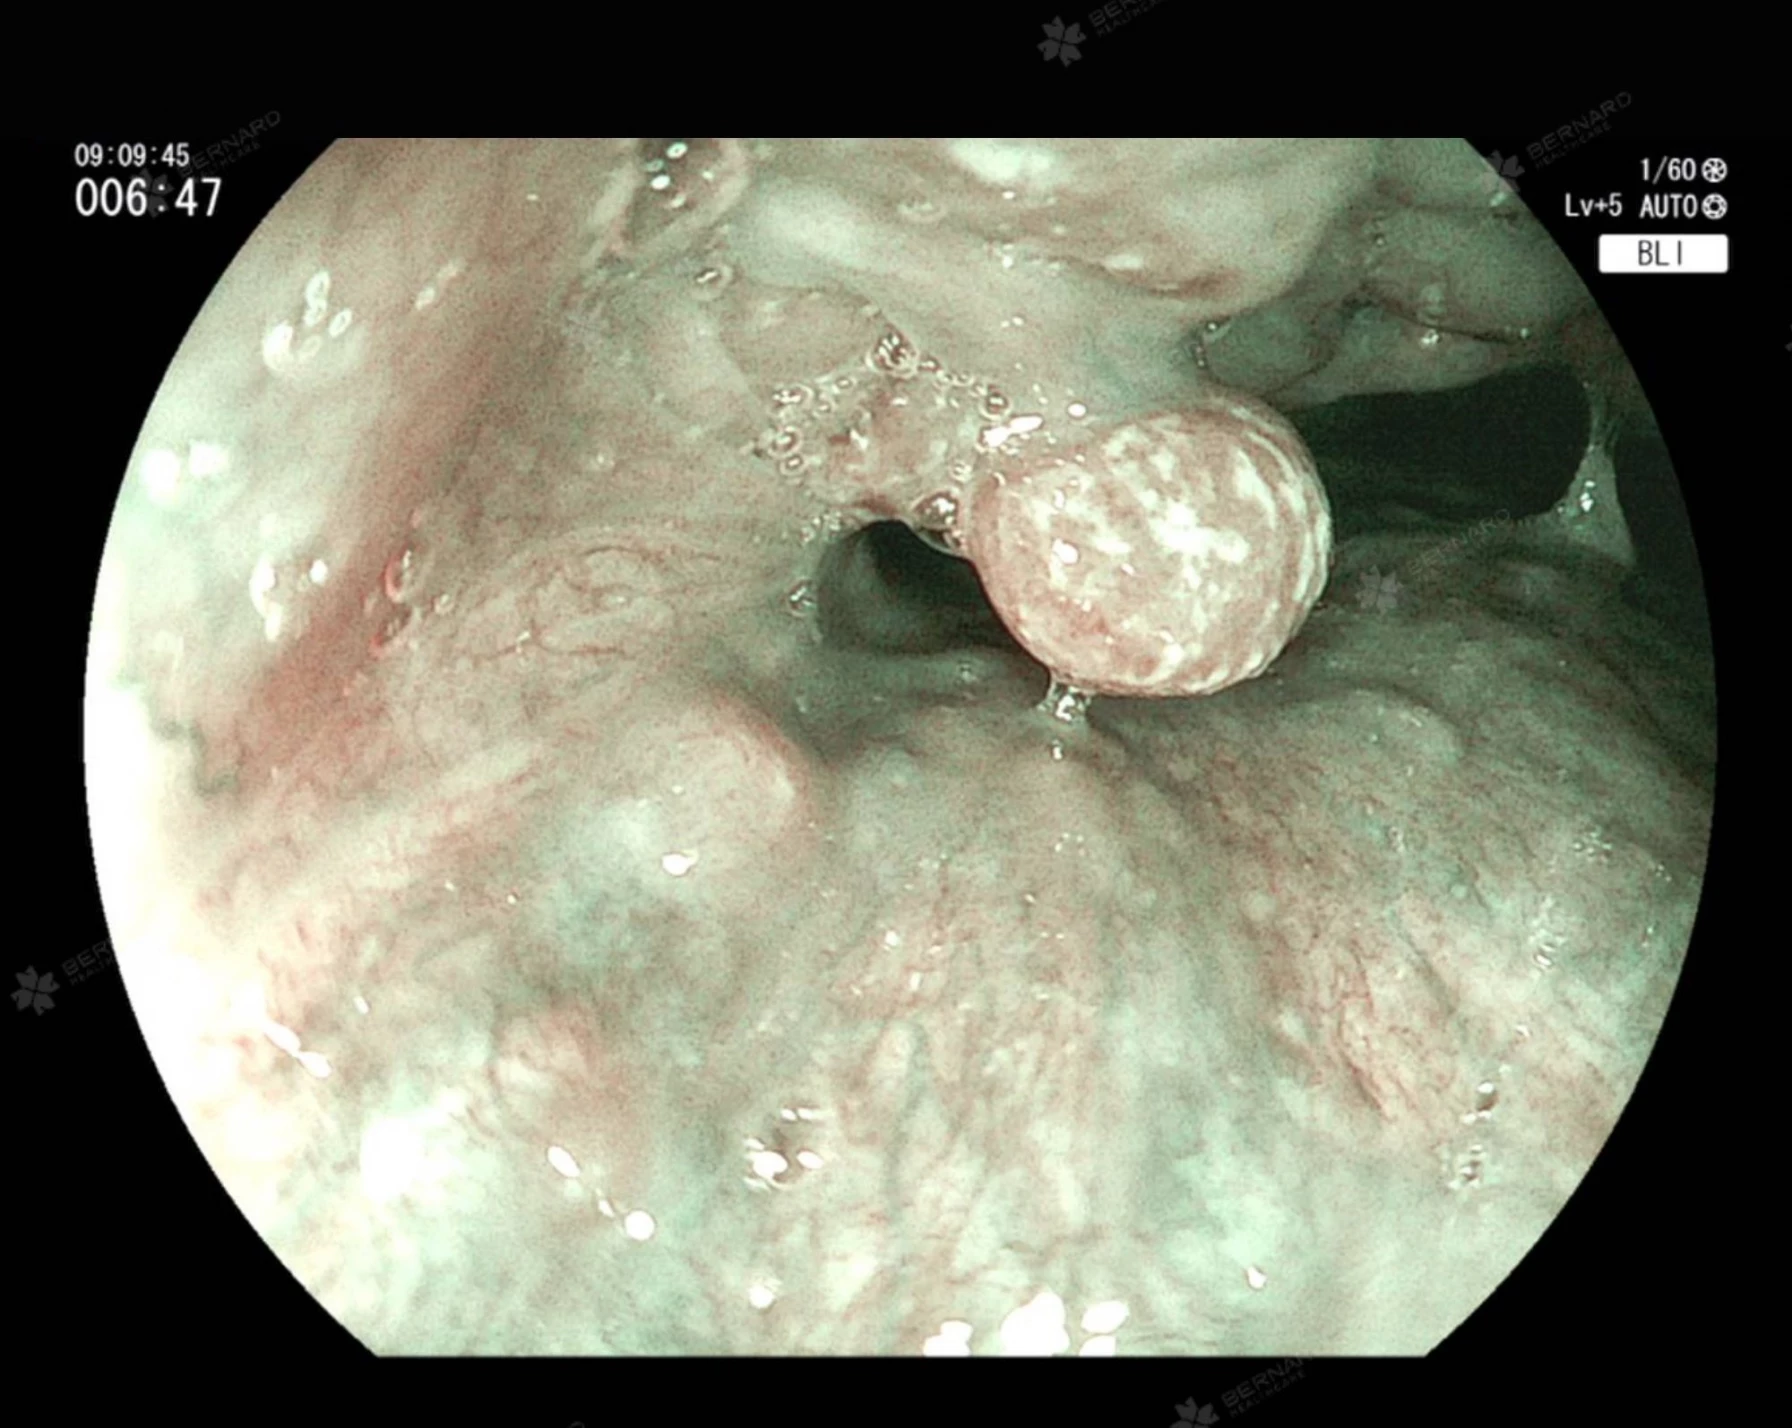

Bernard Healthcare từng tiếp nhận một ca bệnh khiến nhiều người bất ngờ: bệnh nhân nữ 61 tuổi, có tiền sử rối loạn tiêu hóa tái đi tái lại dù đã dùng thuốc điều trị. Theo thời gian, bệnh nhân xuất hiện thêm tình trạng ngưng thở khi ngủ (sleep apnea), ngủ không sâu, mệt mỏi ban ngày. Kết quả thăm khám chuyên sâu cho thấy, vùng hầu họng của bệnh nhân đã hình thành polyp xoang lê - một tổn thương hiếm gặp và dễ bị bỏ sót.

Polyp xoang lê – tổn thương vùng hầu họng dễ bị bỏ qua

Xoang lê (Pyriform sinus) là một cấu trúc giải phẫu nhỏ nằm hai bên thanh quản, thuộc vùng hạ họng - nơi giao thoa giữa đường tiêu hóa và hô hấp. Đây là vị trí có thể mắc dị vật (đặc biệt là xương cá), đồng thời cũng có thể xuất hiện các tổn thương lành tính hoặc ác tính như polyp, ung thư biểu mô hạ họng với tỉ lệ thấp, chỉ khoảng 1 – 4% dân số.